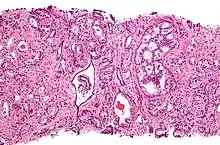

![]() Gleason grade — Lower grades are associated with small, closely packed glands. Cells spread out and lose glandular architecture as grade increases. Gleason score is calculated from grade as described in the text. |

The Gleason grading system is used to help evaluate the prognosis of men with prostate cancer using samples from a prostate biopsy. Together with other parameters, it is incorporated into a strategy of prostate cancer staging which predicts prognosis and helps guide therapy. A Gleason score is given to prostate cancer based upon its microscopic appearance.[1] Cancers with a higher Gleason score are more aggressive and have a worse prognosis. Pathological scores range from 2 to 10, with higher numbers indicating greater risks and higher mortality. The system is widely accepted and used for clinical decision making even as it is recognised that certain biomarkers, like ACP1 expression, might yield higher predictive value for future disease course.[2]

The Gleason grade is based on tissue architectural patterns rather than purely cytological changes. These tissue patterns are classified into 5 grades, numbered 1 though 5. Lower numbers indicate more differentiation, with pattern 5 being the least differentiated.[4][7] Differentiation is the degree to which the tissue, in this case the tumor, resembles native tissue. Greater resemblance (lower grade) is typically associated with a better prognosis.